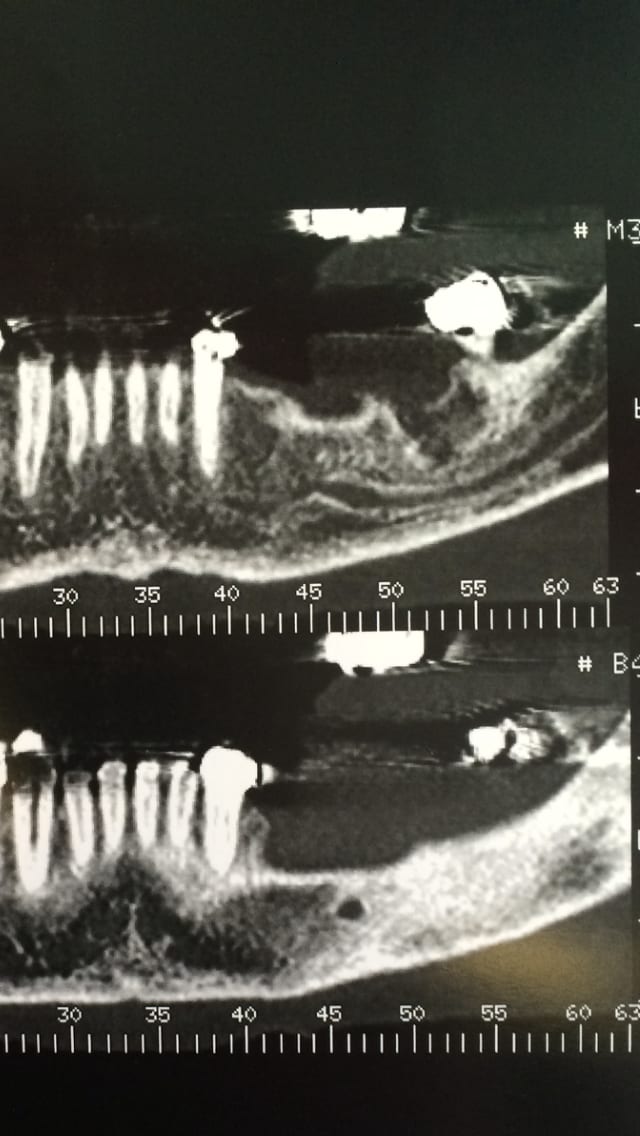

Bonjour je vous envoie quatre coupes je sais c est pas terrible comme image mais je ne sais pas extraire des fichiers proprement pour les mettre sur le forum

Pensez vous a un dédoublement du ndi merci d avance pour vos réponses

C au niveau 36

Bonsoir je sais que l image n est pas terrible mais d après les coupes personne parmi les experts en implantologie peut me dire si c est une vacuole ou un dédoublement je dois bientot poser l implant et j ai pas envie de faire une connerie

Bonjour voilà d autres coupes en vous remerciant par avance de votre avis

Bonsoir personne n à d avis dédoublement ou vacuole?

tu peux avoir un second foramen en position canine mais dans ce cas il s'agit de la prolongation du nerf dentaire inférieur et de l'artère alvéolaire inférieure qui se prolonge jusqu'aux incisives. généralement cette configuration ce retrouve sur des mandibules volumineuse avec une proéminence mentonnière importante.

Il n y a qu un foramen en sortie donc à ton avis pas de dédoublement entre 35 et 36 zone où il y a un peu plus d os et où je veux mettre un 8mm